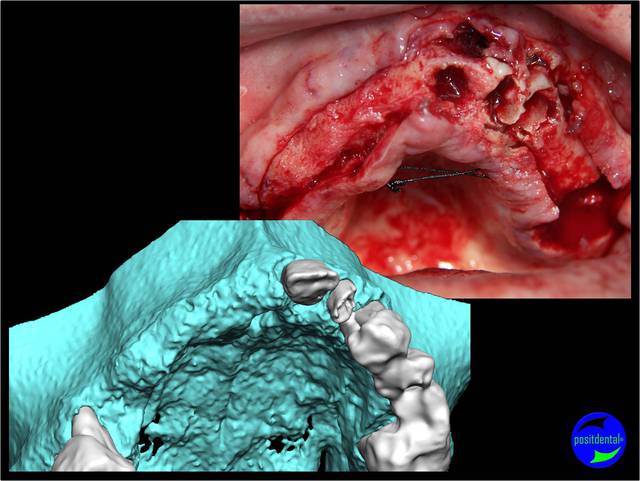

La vidéo présente à partir des plans de traitements, des chirurgies de beotien , des dispositifs médicaux sur mesure positdental et positguide la mise en charge immédiate post-extractionnelle d’un bridge provisoire à armature métal en prothèse fixe sur implants cône morse donc sans vis de maintien. Une question est émise « comment obtient-on ce résultat ? ». Une partie des réponses comme la prédictibilité, la reproductibilité peuvent y être déduite pour d’autre il faudra la bonté de beotien de faire partager les résultats clinique.il nous fait la générosité de poster la phase cicatriciel à 7 jours et des photos de la chirurgie sur un cas.

Si tu as suivi les cas présentés depuis plusieurs années les bridges provisoires ont une armature métal pour la rigidité du fixateur externe, l’intervention se déroule en 1 seul temps chirurgical donc sans prise d’empreinte, c’est pour cela que je parle de MCI. Pour la passivité du bridge avec le système Nobel Guide et leurs piliers expansifs je n’ai vue aucun cas clinique présenté sur le forum. As-tu déjà utilisé le procédé ? Dans les cas présentés sur la vidéo, aucune clé de positionnement n’a été utilisée, le placement des piliers se fait selon la simulation implantaire assistée par ordinateur, leurs présentations a été faite en prospective par OTP, modèle 3D et à la demande de beotien la solution pilier fixe a été retenu à la place du bridge transvisé. Quel sont les compléments d’information que tu as besoin et ou la photo ne te suffi pas ? Pour le protocole d’une MCI, empreintes des maxillaires, dimension verticale de l’occlusion, définition de l’esthétique souhaitée, prescriptions, réalisation du Positscan, traitement des informations à partir des données DICOM, simulation implantaire assistée par ordinateur, validation, réception des DMSM selon les types d’implants et encastillages les procédures varient. Quel système implantaire utilise-tu ?